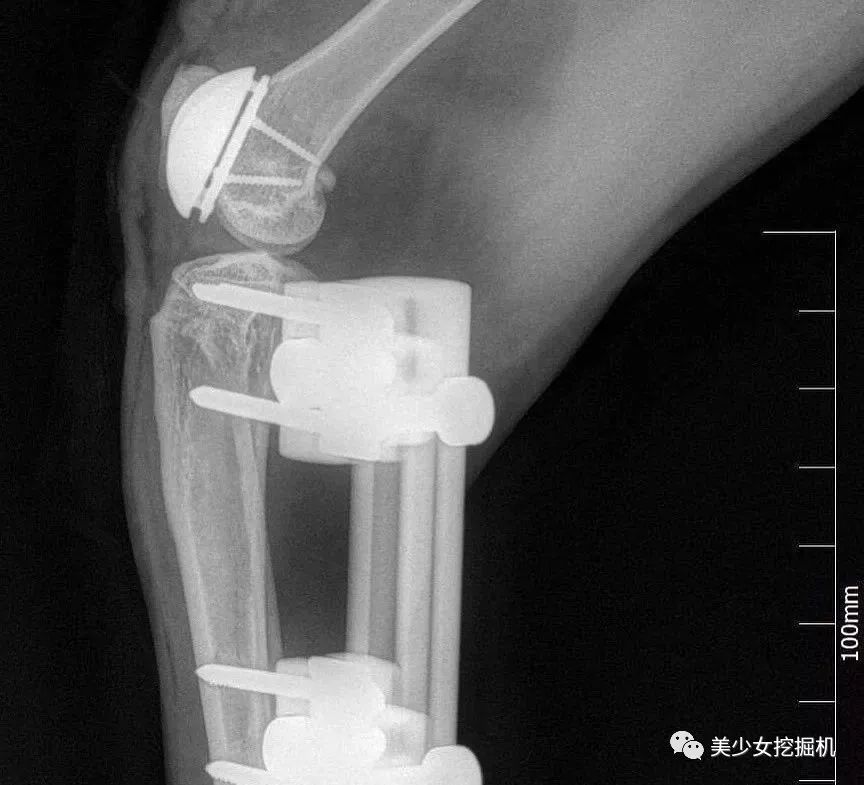

只是赶到医院的时候,Vito的一条后腿已经被车碾碎了,只能截肢,而另一条腿医生在努力抢救了一段时间后,因为严重感染也只能截肢才得以保住性命。就这样,一只原本活蹦乱跳的小橘猫失去了两条后腿。

就在主人不知所措时医生马西莫·佩塔佐尼提出了建议:“如果是我的猫,我会让它尝试假肢看看。”

医生的话点醒了Silvia,凡是生命都应该珍惜,不试试怎么知道它不行。Silvia同意了医生的建议,给Vito按上了假肢。

一段时间后,Vito接受了假肢的存在,在Silvia耐心的帮助下Vito学会了走路、跑步甚至是跳跃。